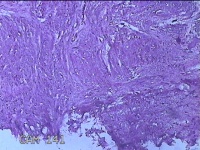

右膝前瘢痕增生组织

性别

女

年龄

38岁

临床诊断

右膝前瘢痕增生

一般病史

右膝前外伤后瘢痕增生4年余。

标本名称

大体所见

灰白粉红色组织6.5x5x1.8cm一块,表面光滑,切面灰白粉红色,质软。